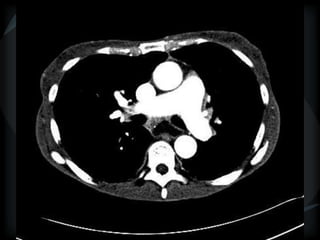

PHTN – PA 39mm

39.2mm

PHTN and septal thickening

? PVOD